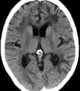

Polycystic osteodysplasia with progressive dementia

Polycystic lipomembranous osteodysplasia with sclerosing leukoencephalopathy is a rare disease characterised by early-onset dementia and multifocal bone cysts. It is also known as Nasu–Hakola disease. [Source: Wikipedia ]